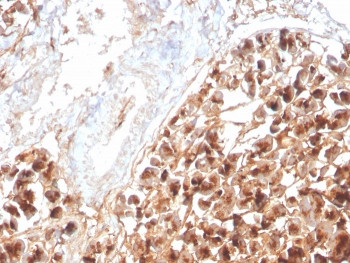

Product information "Anti-Eosinophil Peroxidase, clone rEPO104"

1 mg/ml in 1X PBS, BSA free, sodium azide free. Peripheral blood granulocytes are classified into neutrophils, basophils and eosinophils according to the staining characteristics of their cytoplasmic granules. Granule proteins are released by physiologic and pharmacologic stimuli and play important roles in both normal and pathological host immune responses. Eosinophil major basic protein and eosinophil peroxidase (EPX) are granule proteins specific to the eosinophil. AHE-1 recognizes human EPX, a granule protein specific to eosinophils. It does not cross-react with eosinophil major basic protein, elastase, cathepsin G, esterase N, thrombin, plasmin, kallikrein, lactoferrin, or transferrin. This MAb stains eosinophils only and does not stain other peripheral blood cells, including platelets, neutrophils, monocytes, lymphocytes or red blood cells. Human EPX gene product can form a tetramer of two light chains and two heavy chains. Other peroxidase family members include myeloperoxidase (MPO), lactoperoxidase (LPO), and thyroid peroxidase (TPO). Protein function: Mediates tyrosine nitration of secondary granule proteins in mature resting eosinophils. Shows significant inhibitory activity towards Mycobacterium tuberculosis H37Rv by inducing bacterial fragmentation and lysis. [The UniProt Consortium]

| Application: | IHC (paraffin), FC, IF |